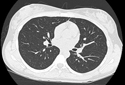

A CT scan is a diagnostic test that takes cross sectional pictures of the patient's internal anatomy. A CT scan creates highly detailed, cross sectional images of body parts and internal organs. CT can show bone and soft tissue structures such as internal organs, muscles, and blood vessels. It can be utilized to detect and diagnose a wide variety of medical conditions and abnormalities of nearly any body organ. A CT scan may require a contrast media such as barium or IV contrast to better highlight abnormalities. These examinations are performed by certified technologists, and every examination is directly supervised and interpreted by board certified radiologists.

A CT scan is made up of a series of x-rays which are processed by a computer to produce cross-sectional pictures of the body. These cross-sectional images allow one to look at the inside of the body.

- Chest